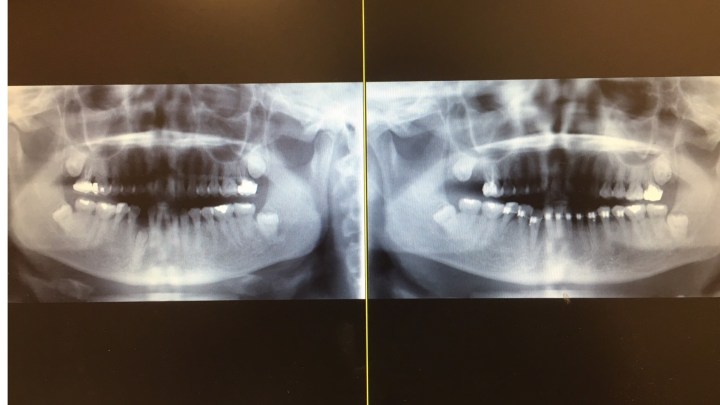

右下犬齒被擋住

黃醫師幫這位媽媽照了張X光片,原來這位媽媽的右下犬齒上面有一顆多生牙,所以把她的犬齒擋住,所以導致犬齒長不出來。

右下犬齒漸漸冒出